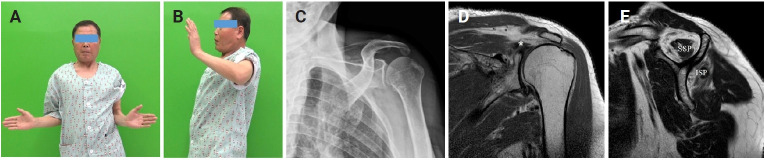

Abstract Image